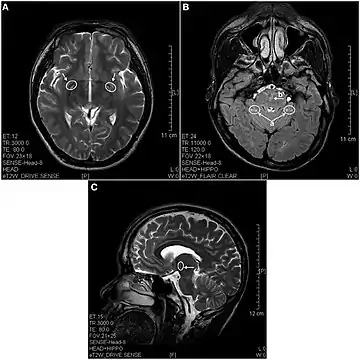

In 2013 a study using magnetic resonance imaging showed brain lesions in ketamine addicts (using from 0.2g twice a week up to 1g daily for 0.5 up to 12 years) with severity depending on the duration of addiction and daily intake of ketamine. Cortical atrophy and holes in superficial white matter are seen early on. After 4 years of addiction lesions spread throughout the brain and damage is evident in the pons and other deeper brain structures.[16]